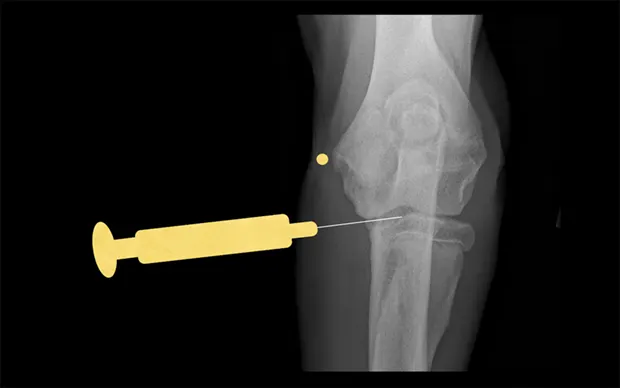

Stifle

Place the patient in dorsal recumbency with the stifle flexed to a 90° angle. The fat pad of this joint may hinder aspiration of joint fluid. Insert a 22-gauge, 1.5-inch needle just medial or lateral to the patellar ligament and about half the distance from the tibial crest to the patella. The needle should aim toward the intercondylar notch.

Lateral view of stifle. Insert the needle medial or lateral to the patellar ligament toward the intercondylar notch.